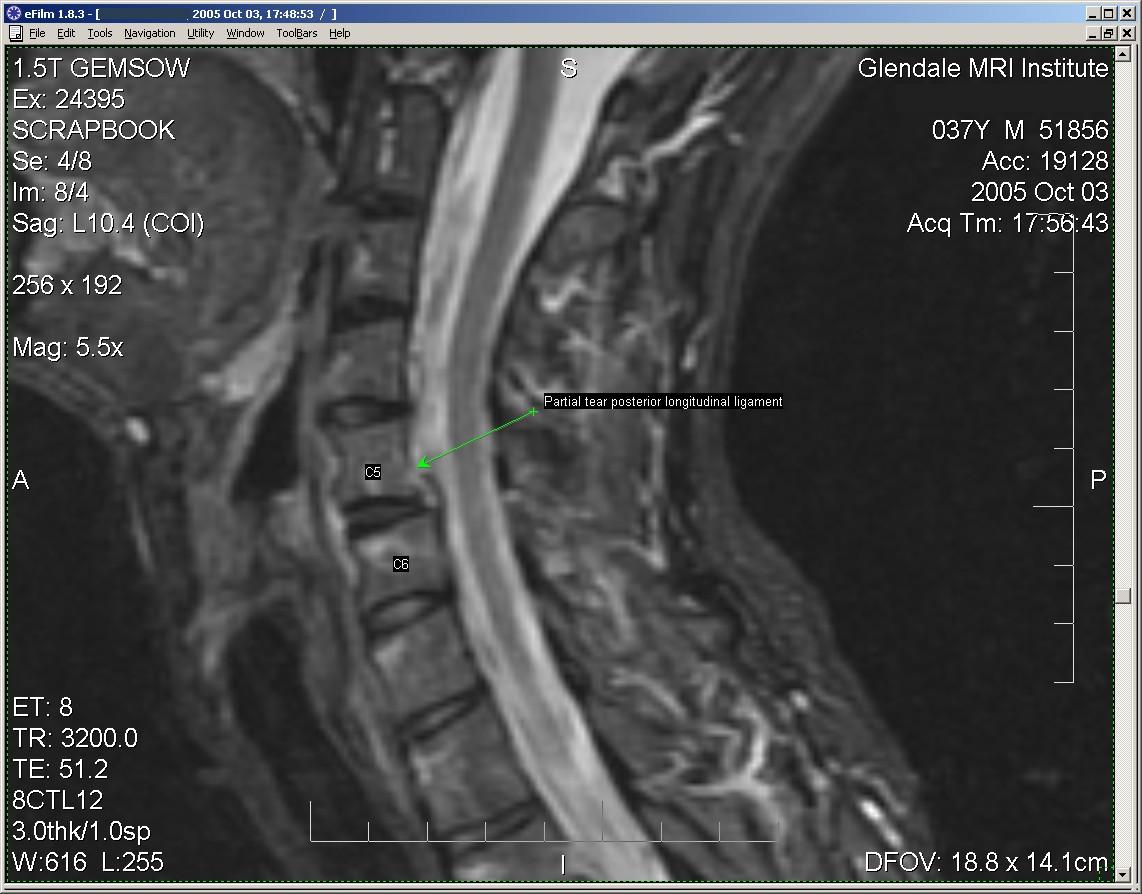

Here is a partial tear of that posterior longitudinal ligament. It is this tear that allows your C5 vertebral body to shift relative to C6 when subjected to stress.